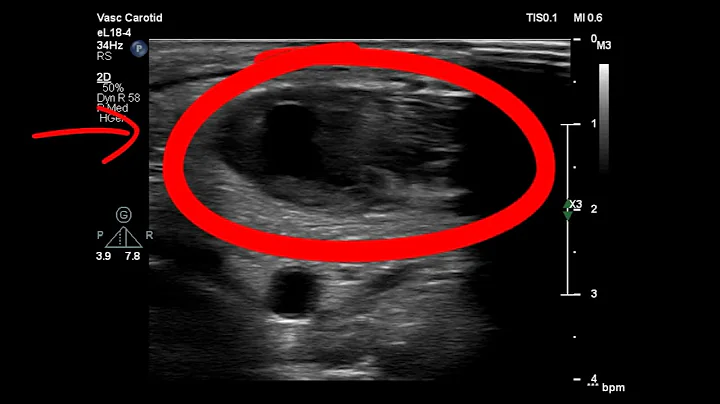

V7 - 3 Week Jugular Vein Decompression Surgery Update

3 week update, and I am sore, but recovering. If you'